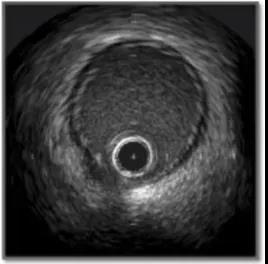

IVUS所示的正常冠脉的血管影像可见3层组织,两个分界面,即管腔-内膜交界面和中膜-外膜交界面(图4)。

图4. IVUS所示的正常冠脉的血管影像